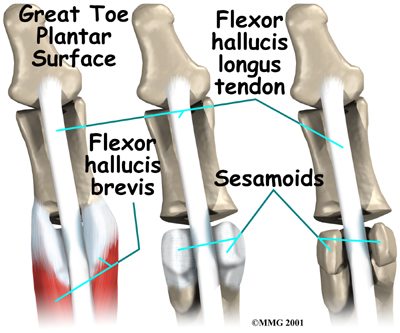

The muscles that bend the big toe down (the toe flexors) pass underneath the main joint of the big toe, crossing over the bump formed by the sesamoid bones. This bump acts as a fulcrum point for the toe flexors, giving these muscles extra leverage and power. The sesamoids also help absorb pressure under the foot during standing and walking, and they ease friction in the soft tissues under the toe joint when the big toe moves.

Bone Removal

Your surgeon may recommend removing part or all of the sesamoid bone. When bone is removed from only one sesamoid, the other sesamoid bone can still provide a fulcrum point for the toe flexors. However, if both of the bones are taken out, the toe flexors lose necessary leverage and can't function. When this happens, the big toe will either bend up like a claw or slant severely toward the second toe. Thus, surgeons usually try to avoid taking both sesamoids out.